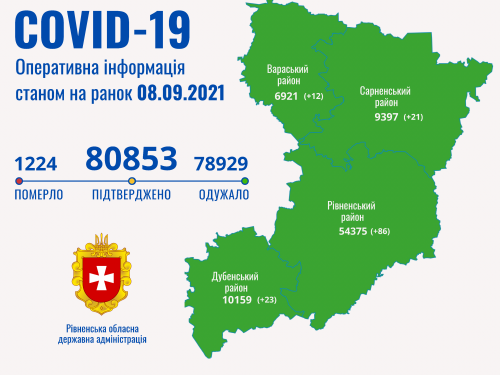

Коронавірус повертається: як стрімко зростає кількість хворих на Рівненщині (ВІДЕО)